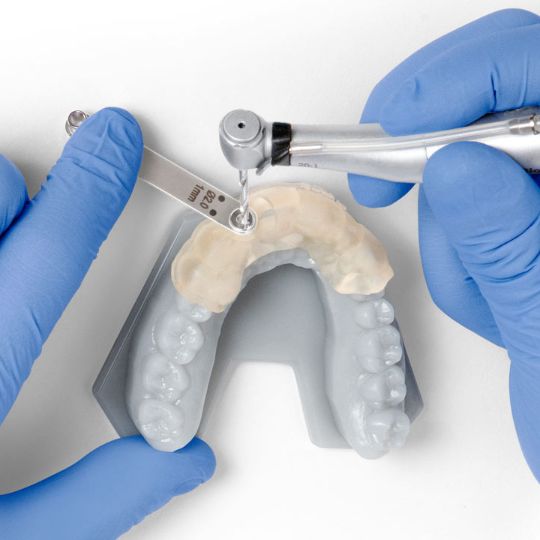

Этап 2. Хирургический этап

Установка имплантатов проводится при использовании специального хирургического шаблона. Этот шаблон позволит хирургу-имплантологу установить имплантаты в челюсть в заранее спланированное место, под абсолютно правильным углом и на заранее определенную глубину с точностью до долей миллиметра.